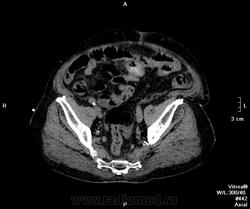

Пациент оперирован по поводу аденоКа толстого кишечника, гемиколэктомия. Онкопоиск, поиск вторичного поражения.

В воротах печени беда, но не об этом сейчас. Прицельно смотрим контраст.

Артериальная.

Венозная.

отсроченные

Случай 2. Опять не попали в фазы, рано. Исследование малоинформативно по сути(. Какова скорость введения автошприцем? Катетер кубитальный или в запястье?